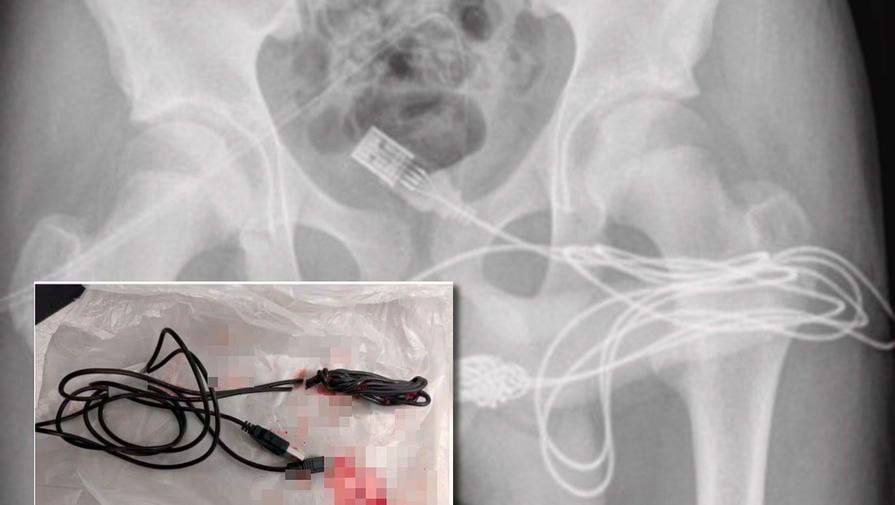

Deep Urethral Sound 149 photos